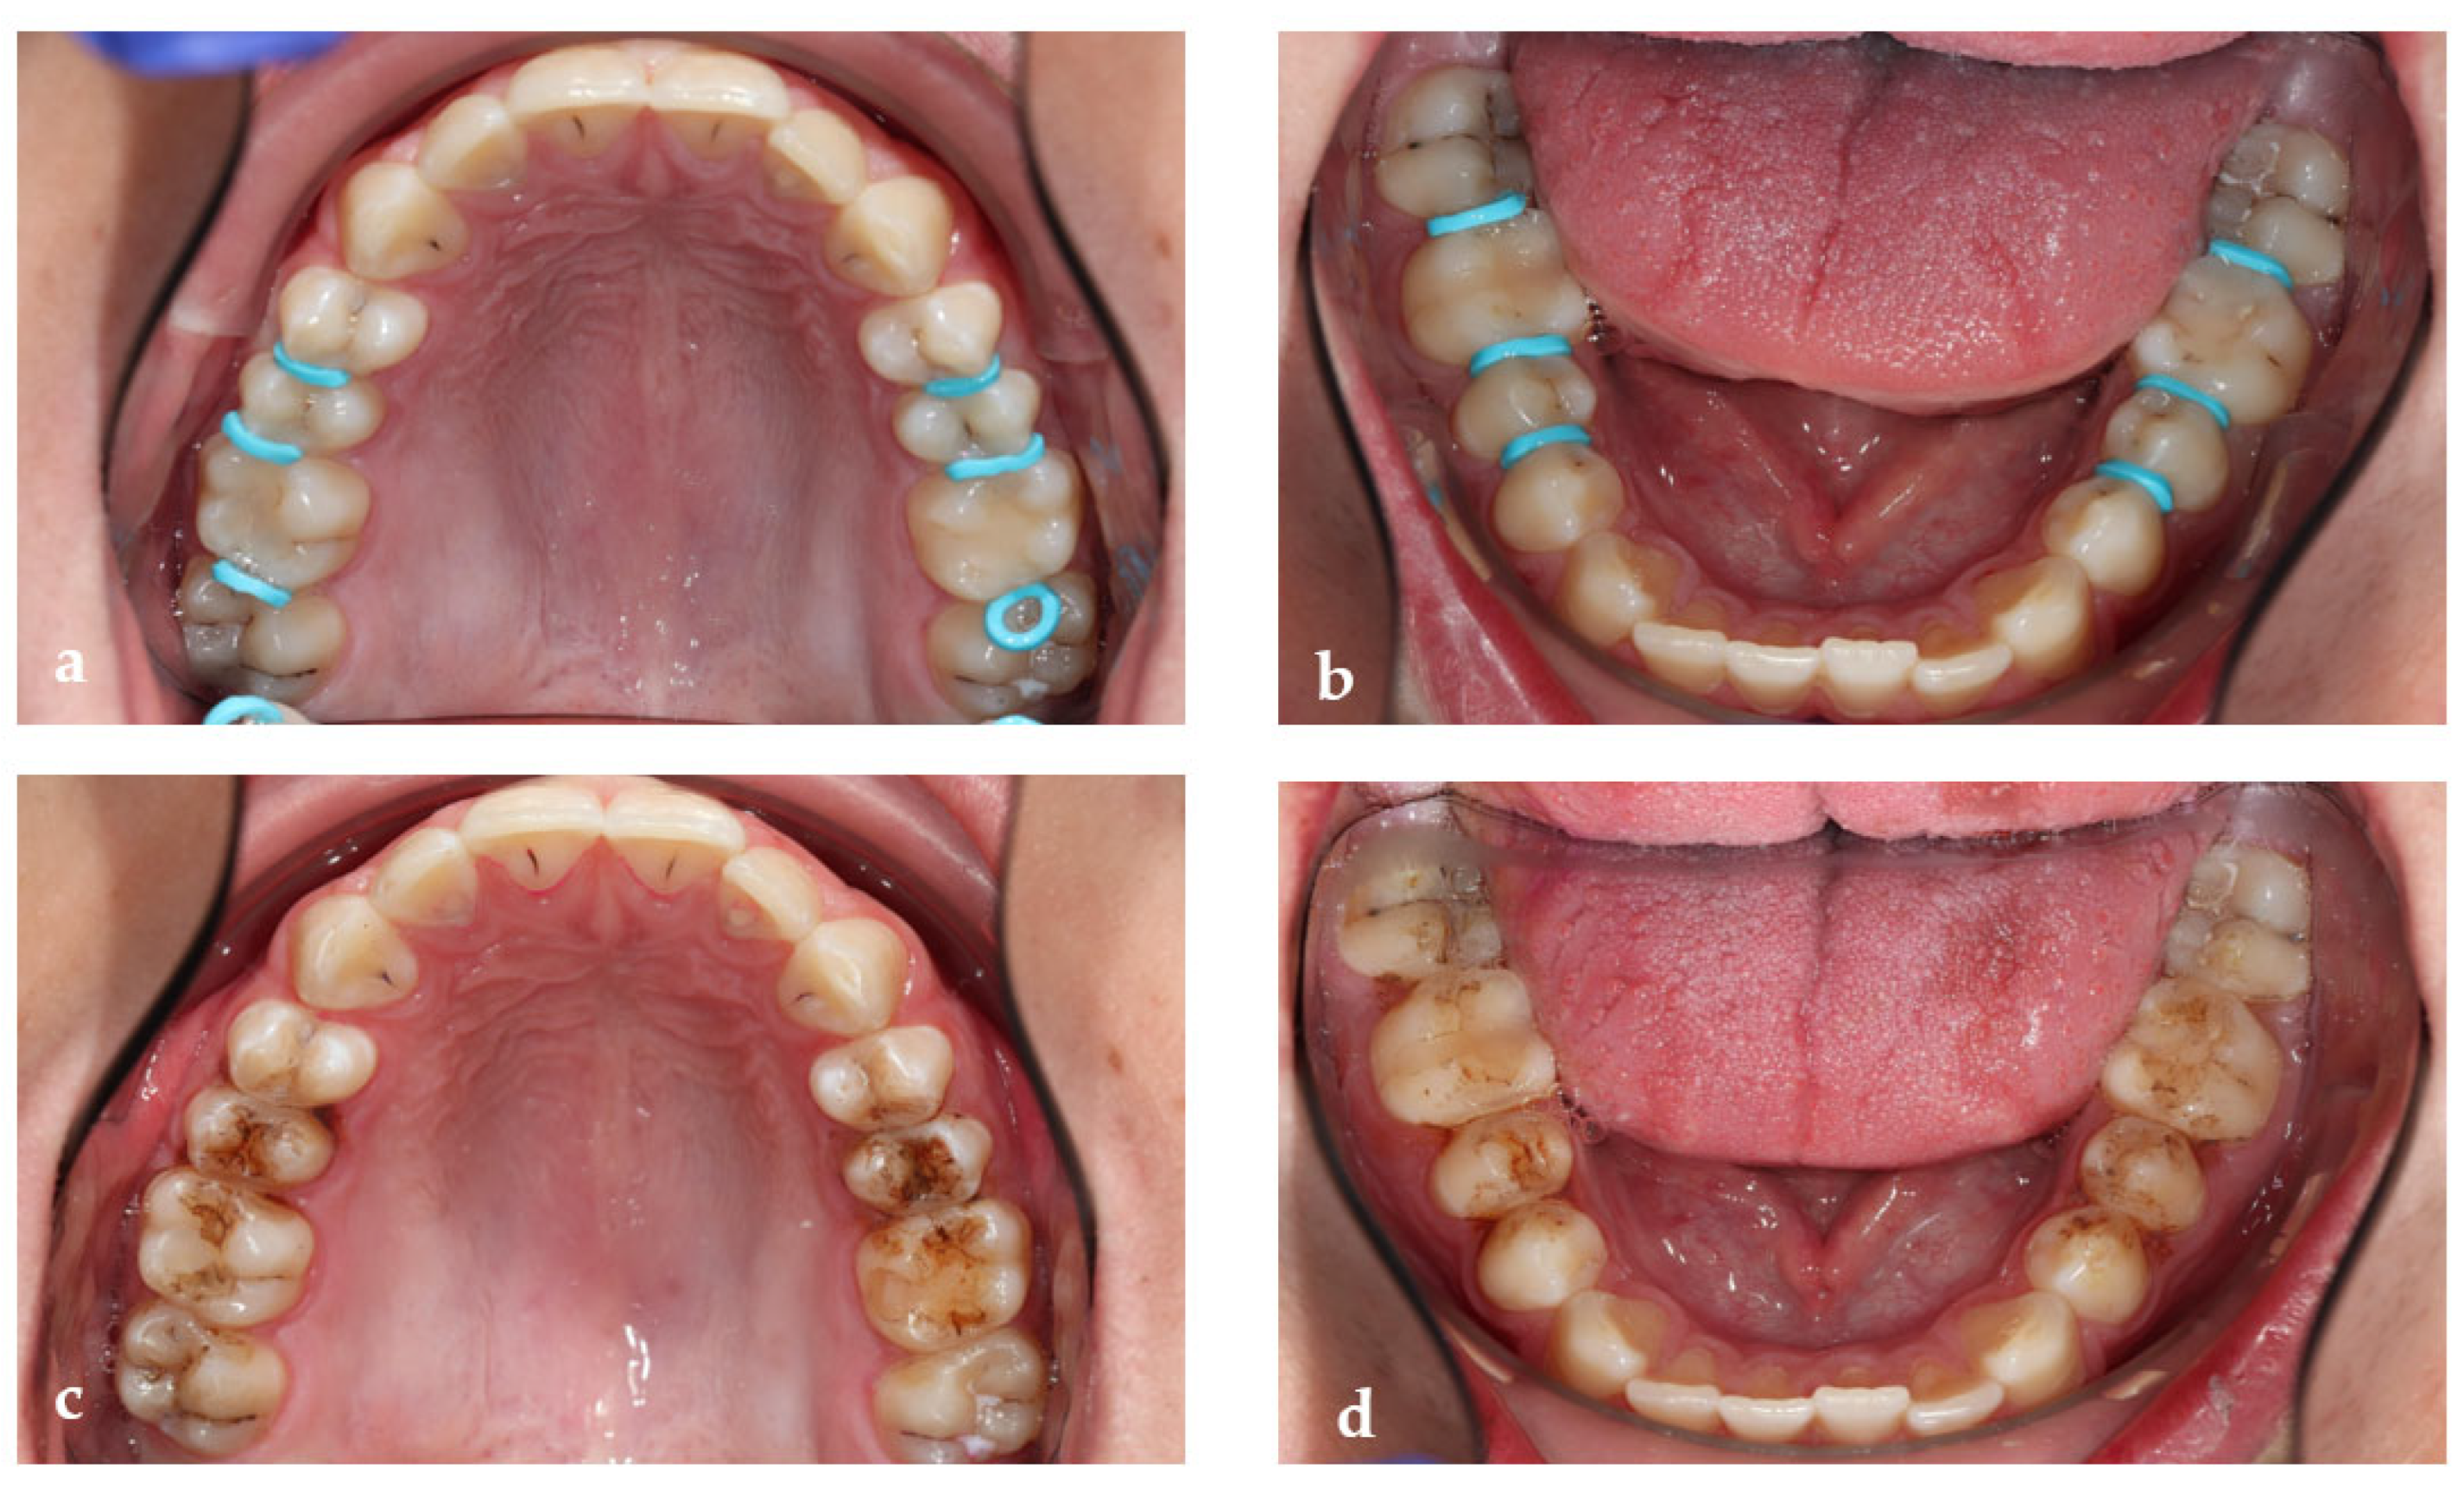

- Tooth separation with orthodontic rubbers: This revealed the absence of cavitation (Figure 3a,b).